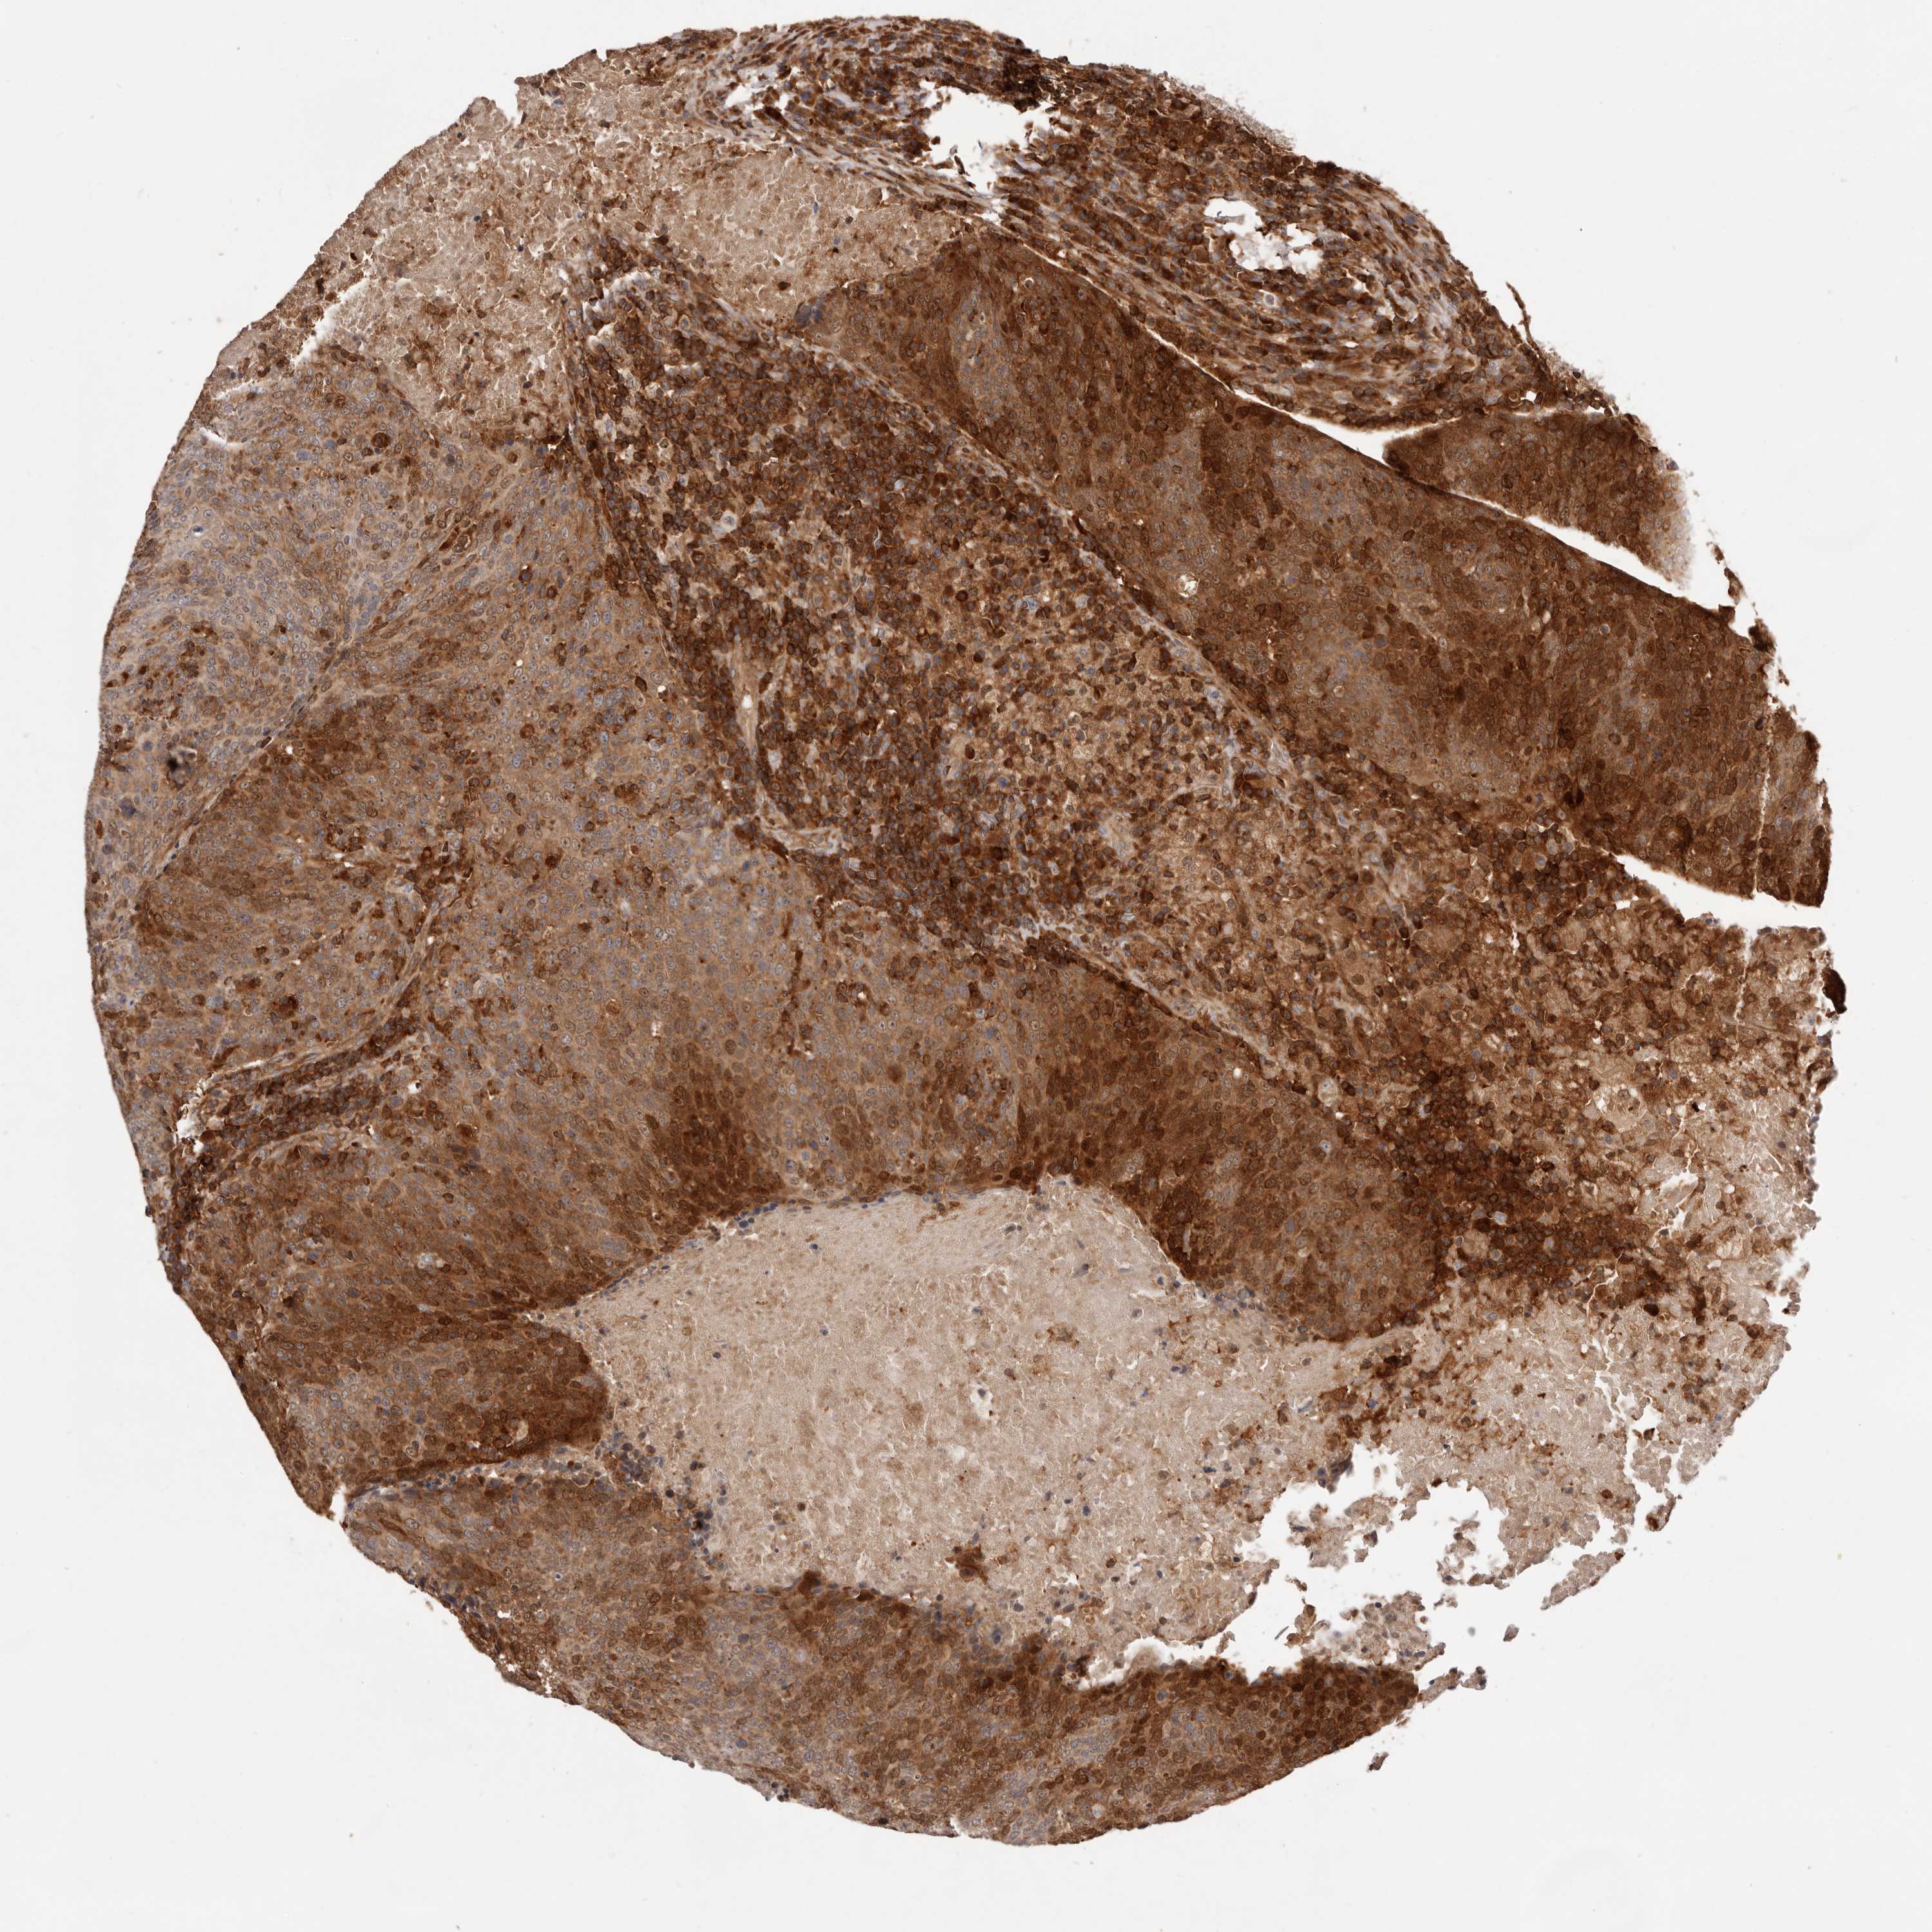

HEAD AND NECK CANCER - Protein expressioni

A mouse-over function shows sample information and annotation data. Click on an image to view it in a full screen mode. Samples can be filtered based on level of antibody staining by selecting one or several of the following categories: high, medium, low and not detected. The assay and annotation is described here.

Antibody stainingi

Antibody staining in the annotated cell types in the current human tissue is reported as not detected, low, medium, or high, based on conventional immunohistochemistry profiling in selected tissues. This score is based on the combination of the staining intensity and fraction of stained cells.

Each image is clickable and will lead to virtual microscopy that enables deeper exploration of all samples and also displays staining intensity scores, fraction scores and subcellular localization as well as patient and tissue information for each sample.

Antibody HPA003347

Staining

High

Medium

Low

Not detected

Intensity

Strong

Moderate

Weak

Negative

Quantity

>75%

75%-25%

<25%

None

Location

Nuclear

Cytoplasmic/membranous

Cytoplasmic/membranous,nuclear

Squamous cell carcinoma, NOS